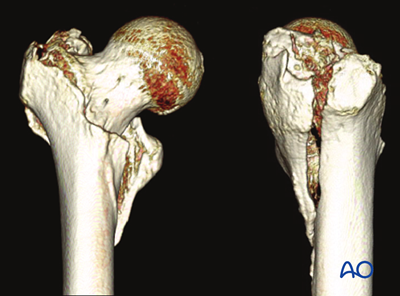

Revised proximal femur fracture management

This revision brings a whole set of new features. Theerachai Apivatthakakul (Thailand) and Jong-Keon Oh (South Korea) provided up-to-date expertise with Michael Baumgaertner (United States) as the editor. The module now contains pages on patient assessment, complications and technical failures, and assessment of reduction quality. Special emphasis is given to describing simple and complex pertrochanteric fracture patterns with illustrations and clinical cases. A section on the management of combined fractures has been added, and sliding hip screw, cancellous screw fixation, nailing, and arthroplasty techniques have been updated.